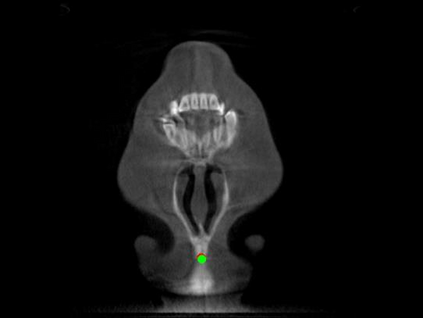

Detecting 3D landmarks on cone-beam computed tomography (CBCT) is crucial to assessing and quantifying the anatomical abnormalities in 3D cephalometric analysis. However, the current methods are time-consuming and suffer from large biases in landmark localization, leading to unreliable diagnosis results. In this work, we propose a novel Structure-Aware Long Short-Term Memory framework (SA-LSTM) for efficient and accurate 3D landmark detection. To reduce the computational burden, SA-LSTM is designed in two stages. It first locates the coarse landmarks via heatmap regression on a down-sampled CBCT volume and then progressively refines landmarks by attentive offset regression using multi-resolution cropped patches. To boost accuracy, SA-LSTM captures global-local dependence among the cropping patches via self-attention. Specifically, a novel graph attention module implicitly encodes the landmark's global structure to rationalize the predicted position. Moreover, a novel attention-gated module recursively filters irrelevant local features and maintains high-confident local predictions for aggregating the final result. Experiments conducted on an in-house dataset and a public dataset show that our method outperforms state-of-the-art methods, achieving 1.64 mm and 2.37 mm average errors, respectively. Furthermore, our method is very efficient, taking only 0.5 seconds for inferring the whole CBCT volume of resolution 768$\times$768$\times$576.